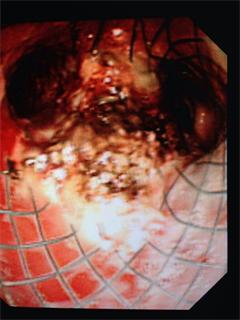

今日,我科俞万钧副院长医疗团队再次为一舟山患者进行了全麻下支气管镜下热消融术。该病人为食道癌晚期患者,1年前在上海行手术治疗,但术后迅速复发,近一月来症状加重明显,稍微活动既感气促明显,当地医院支气管镜检查见肿瘤已蔓延至气管下端,双侧主支气管,左侧更是完全阻塞,当地医院束手无策。经介绍,患者1周前来我进一步诊治,进我科室时,患者难以行走,平躺,需侧卧,无法连续说话,气促明显,饱和度不稳,随时可能窒息死亡。经积极对症处理,待患者生命体征好转后,俞万钧副院长紧急行支气管镜下热消融,打通左主支气管,DSA下放置Y型支架。患者症状立即好转,次日回家。本次复查支气管镜,见患者肿瘤生长旺盛,覆盖大部分支架,再次阻塞左主支气管。俞万钧副院长再次主刀,行支气管镜下热消融术,打通左主支气管,为患者缓解痛苦,延长患者生命周期,提高了患者的生活质量。我科近年来在俞万钧副院长的带领下,在晚期肺癌介入领域不断探索,发展,开展了一系列国内先进的介入手术,为相当一部分晚期肿瘤患者带来福音。(徐涛)